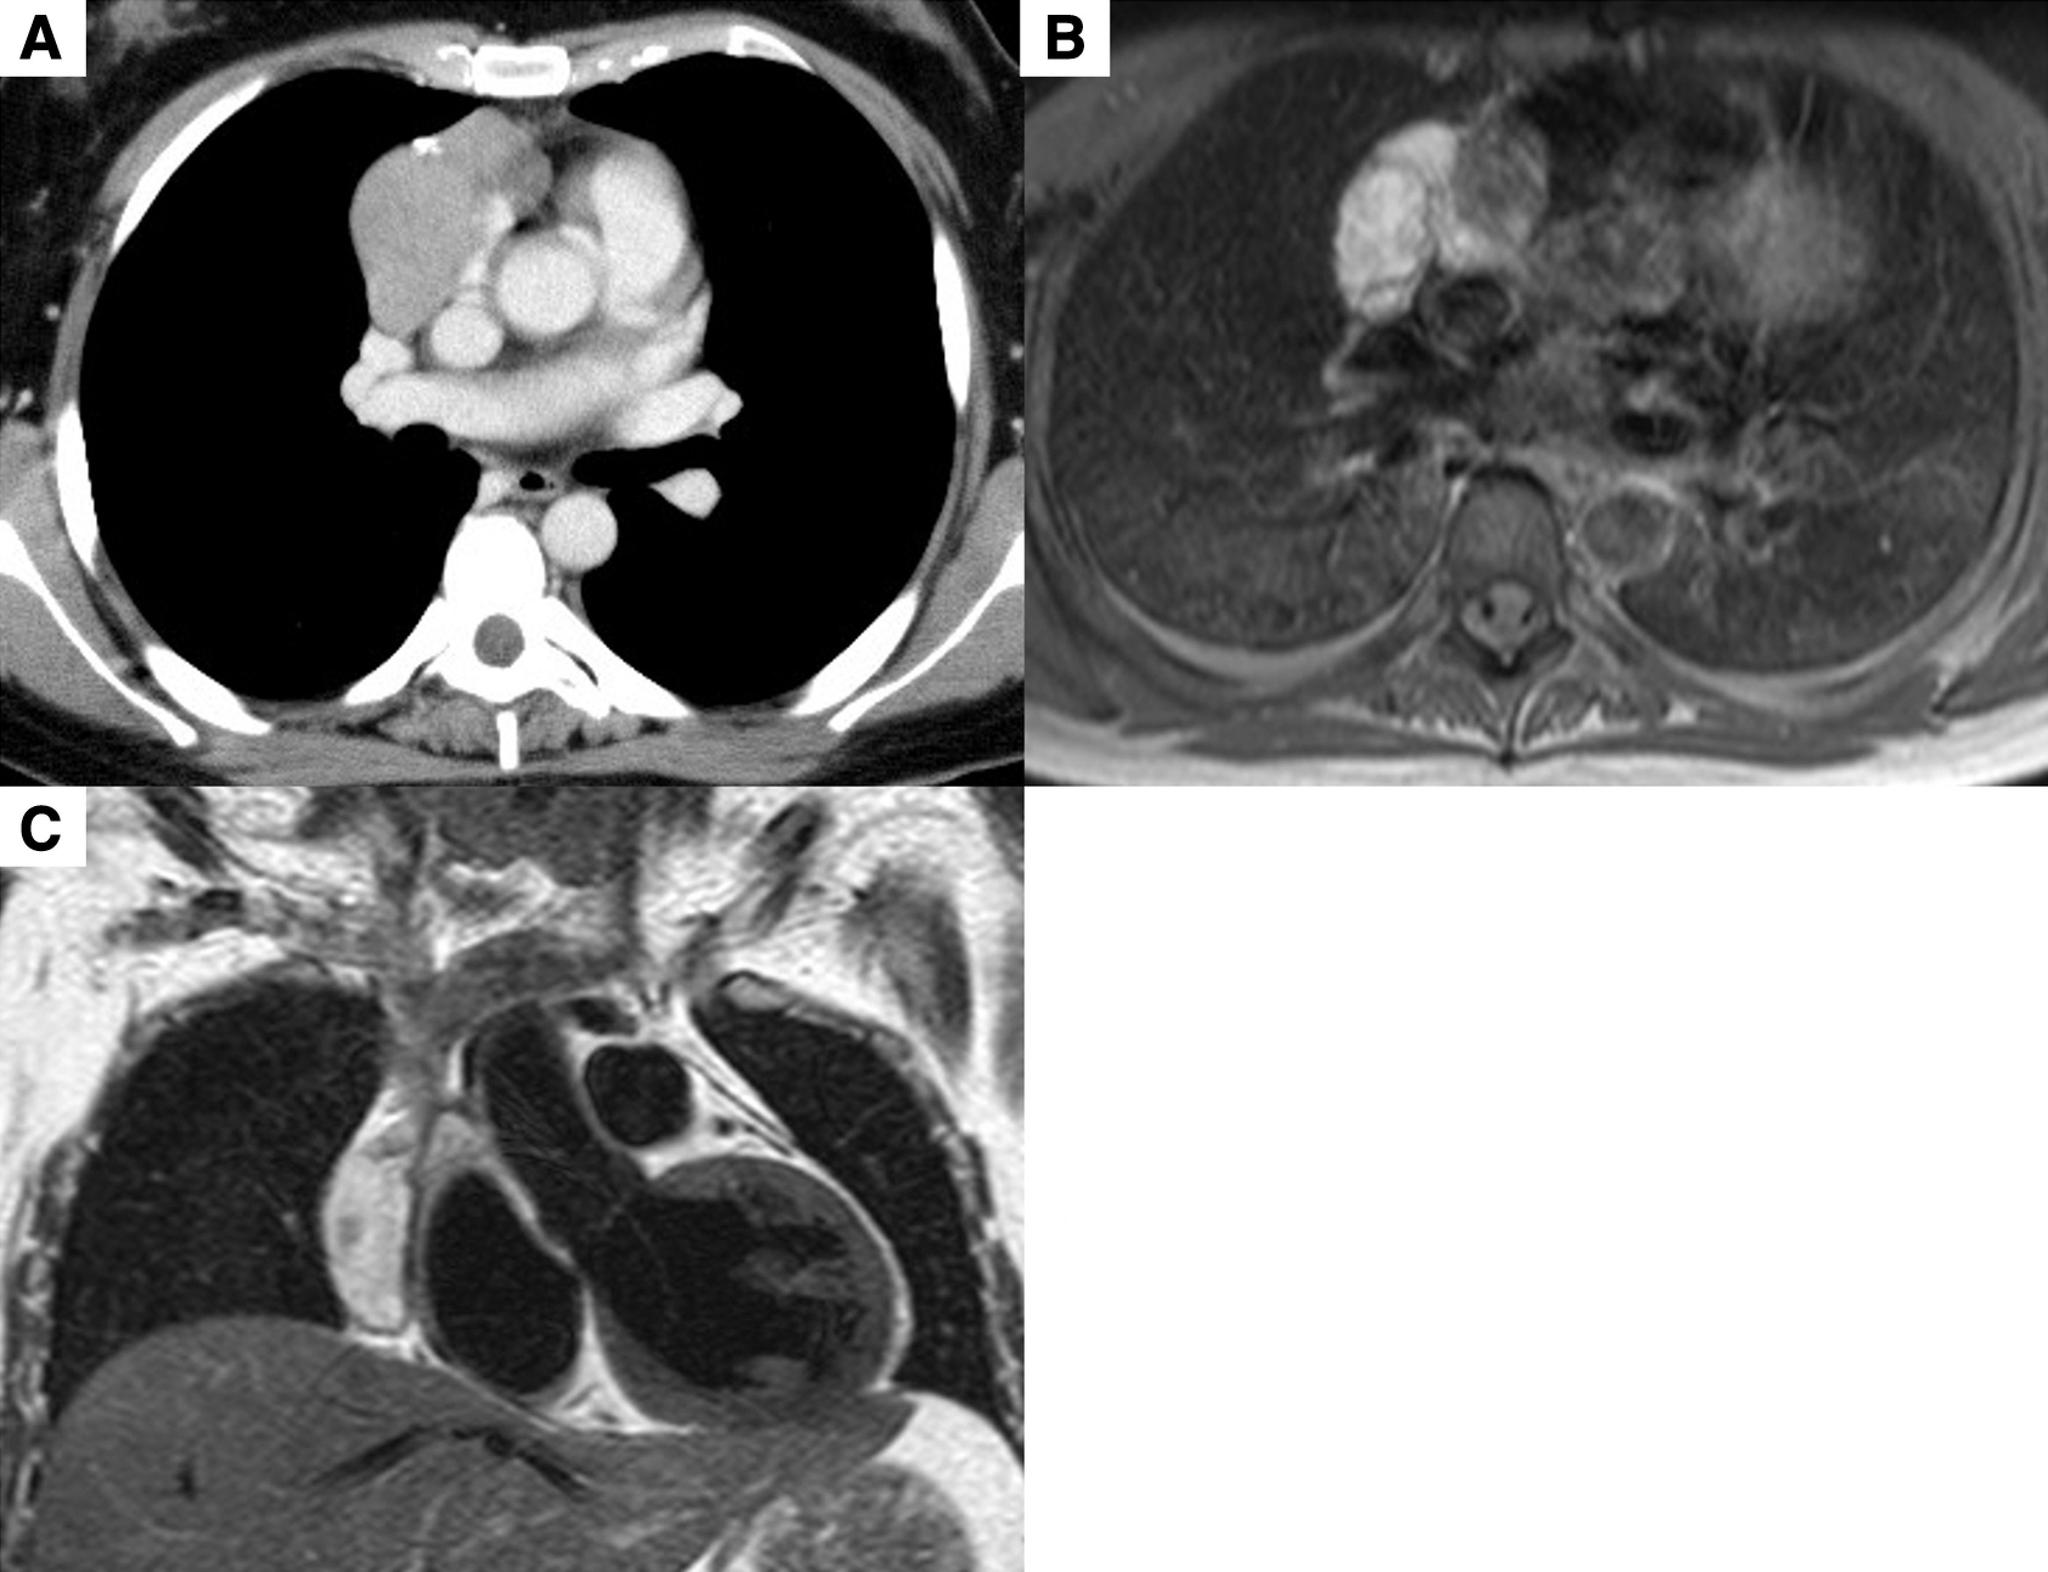

A 26-year-old woman presented with lower limbs convulsions and gait disturbance and complained of leg pain. Cerebrospinal fluid and blood test results showed a high level of anti-glutamic acid decarboxylase (GAD) antibodies. Computed tomography showed anterior mediastinal tumor suggestive of a thymoma. She underwent extended thymectomy, and her symptoms gradually improved after surgery. No evidence of recurrent thymoma and SPS has been observed over 44 months.

一名 26 岁女性因下肢抽搐和步态障碍就诊,并诉腿部疼痛。脑脊液和血液检查结果显示谷氨酸脱羧酶(GAD)抗体水平升高。计算机断层扫描显示前纵隔肿瘤提示胸腺瘤。她接受了扩大的胸腺切除术,术后症状逐渐改善。44 个月后未发现复发性胸腺瘤和 SPS。